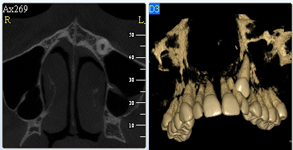

3D DVT - NewTom

Je speciální zubní digitální tříprostorový tomograf (3D), který umožňuje na základě jediného

snímkování vytvořit všechny typy RTG zobrazení, které jsou pro lékaře potřebné. Díky používané technologii tzv. „kuželového paprsku“ a speciálním senzorům je

výrazně zmenšená dávka záření - o více jak 80% proti klasickému CT vyšetření. To je významné zejména u dětí. Pomocí tohoto přístroje je možné zjisti skutečnou situaci v čelistních kostech pacienta tedy množství kosti - můžeme změřit skutečnou šířku i výšku kosti, i kvalitu kosti (hustotu) v místě uvažované implantace. 3D (tříprostorové) zobrazení umožňuje zvýšit prostorovou představu operatéra ještě před vlastní operací a zároveň pacientovi lépe objasnit a ukázat oblast plánovaného zavedení implantátu.

Pacient „neumí číst“ RTG snímky, ale díky 3D zobrazení vidí „svoji skutečnou čelist“

- např. jak je nízká či úzká, vidí průběh nervu nebo velikost čelistní dutiny, což mu umožní i pochopení nutnosti v některých případech provést pomocné zákroky ještě před vlastním zavedením implantátu (viz. kostní štěp, sinus lift, kostní granulát...).

Vyšetření pomocí tohoto přístroje používáme i ve stomatochirurgii (zlomeniny čelistí, zuby moudrosti, cysty, onemocnění čelistního kloubu), ortodoncii (retinované zuby, nadpočetné zuby), parodontologii atd.